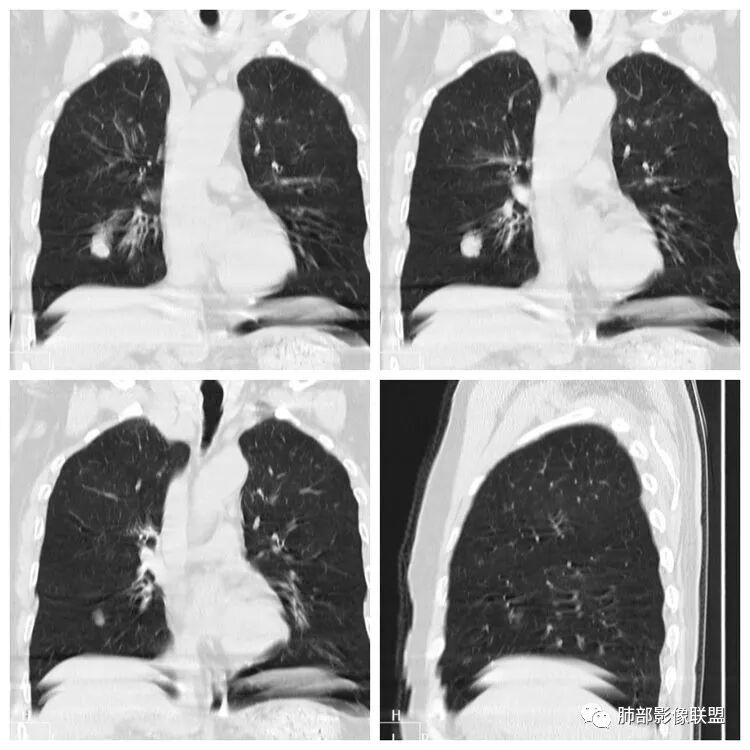

老年女性,吸烟史,右肺中叶外侧段结节,局部突起,浅分叶,右肺中叶外侧段支气管进入截断,病理不会看,无增强,常规考虑1,鳞癌。2,错构瘤。

小兜:老年女性,吸烟史,体检发现右肺中叶外侧段类圆形结节,周围浅分叶,冠状位似见支气管进入后截断,未见脂肪及钙化

综合考虑为良性病变,病理不会看,肺软骨瘤?软骨型错构瘤?

老年男性,66岁,吸烟史38年。右中叶孤立椭圆形结节,边缘光滑,分叶,指状突起?冠状位支气管在病灶边缘截断。病理不会看。考虑:良性结节,错构瘤?鉴别Ca。

患者老年男性,体检发现右肺占位1天。有“高血压、脑出血、胃息肉术后、腰椎压缩性骨折”病史。胸部CT:右肺中叶外侧段紧贴叶间裂不规则实性结节,边界清楚、膨隆,见血管穿行,支气管远端堵塞。结合长期大量吸烟史。考虑恶性病变,病理不会,小细胞癌可能。鉴别鳞癌、错构瘤或平滑肌瘤。

右肺中叶结节,位于叶间胸膜下,无明显胸膜牵拉,说明收缩力不强,结节整体边缘膨隆、分叶,局部局限性突出,像个小尾巴,密度不均匀,可见支气管进入,远端显示欠清晰,病理图不会看,首先考虑小细胞肺癌,鉴别错构瘤,转移瘤

傅昌瑜:老年女性,体检发现右肺结节,长期吸烟史,实性结节,有指状凸起,边缘光滑,与血管及支气管关系不甚清楚。病理图片见密集的核大深染异型细胞。需考虑:1.错构瘤:园,光滑,分叶少,支气管、血管贴边。有时可见黑晕征。无明显强化。病理可见支气管粘膜、平滑肌、软骨及脂肪组织等,患者病理图片中无软骨及脂肪组织。故不考虑错构瘤。2.硬化性肺细胞瘤:与支气管关系密切,强化较明显。病理可见间质卵圆形细胞、血管区、泡沫细胞等。患者病理图片无上述细胞,不支持PSP。3.恶性肿瘤:腺癌:病灶无明显膨胀性生长、无毛刺,不支持;小细胞癌:结节一侧可有指状凸起。病理图片见密集的核大深染疏松的异型细胞考虑小细胞癌。目前考虑小细胞癌可能性大。注意鉴别其他恶性肿瘤

LCNEC最常见的影像特征包括:(1)肿块发生部位:周围型肺癌为主,少数发生于肺中央。(2)肿块大小及形态。因肿瘤细胞生长迅速常形成较大肿块,因此其体积一般较大,直径常在3~10cm范围内,病灶常为不规则形软组织肿块。(3)肿块边界。多数学者报道大多数肿块边界清晰光整,边缘可呈分叶状,收缩能力不强,毛刺征及“胸膜凹陷征”少见,病灶附近常干净。认为与该病对周围组织浸润较轻及较少产生纤维瘢痕组织牵拉有关联。(4)肿块密度、强化特点及代谢情况。据文献报道,该类肿瘤因体积较大CT上常见软组织肿块,部分密度较均匀,病灶较大者可以观察到囊变坏死区,增强后呈轻或中度不均匀强化(可见强化者占75.7%),认为其强化特点与其内部肉眼可见坏死灶和肿瘤较大直径有关。(5)伴随症状及远处转移。该病恶性程度高,侵袭性强,常侵犯邻近结构,如胸膜、心包、邻近骨质或纵隔内组织等,易出现纵隔淋巴结转移,部分发生肺内及远处转移,少数早期可出现广泛远处转移。

LCNEC患者空洞、钙化、阻塞性肺炎、肺不张、积液这些CT特征较少见,少见支气管充气征。